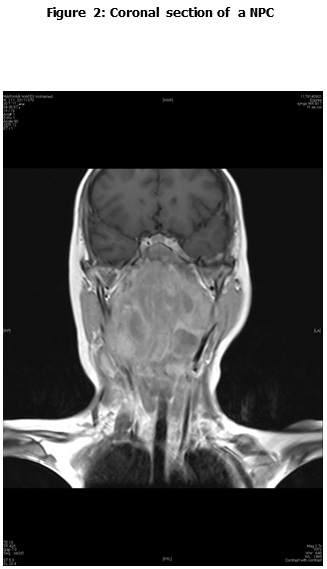

This is a retrospective study including all the newly diagnosed pediatric NPC who were diagnosed and treated at the Children Cancer Hospital Egypt (CCHE) during the period from July 2007 to December 2012. All imaging studies (e.g., CT or MRI scans) were reviewed by a senior head and neck radiologist for proper staging and assessment of tumor response. Patients were staged according to AJCC staging system. Modified version of the Response Evaluation Criteria in Solid Tumor (RECIST) was used to assess response.

This is a retrospective study including all newly diagnosed pediatric NPC at Children Cancer Hospital Egypt CCHE during the time period from July 2007 to December 2012. The patients' profiles were systematically reviewed for characteristics including pathology, laboratory, radiological work up and documented toxicities. All imaging studies (e.g., CT and MRI scans) were reviewed by a senior head and neck radiologist for proper staging and assessment of tumor response.

Pretreatment evaluation included a complete history and physical examination, complete blood count, serum biochemistry tests (including evaluation of electrolyte levels, hepatic and renal function tests), CT or MRI scans of the head and neck region, chest and bone scan. During therapy weekly examinations and laboratory evaluations were performed. Tumor response was assessed by clinical examination with appropriate MRI imaging studies after completion of neoadjuvant chemotherapy and at the end of radiotherapy.